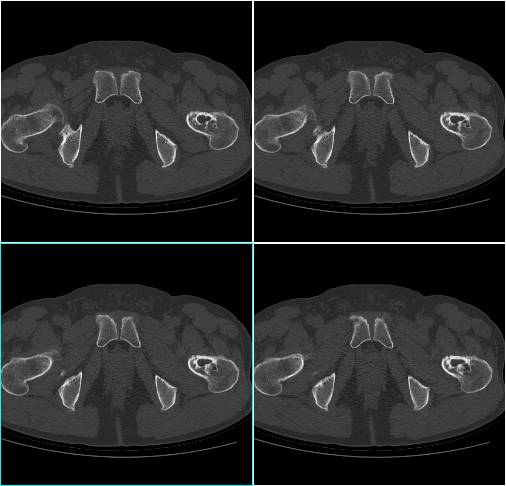

X线特征相当典型,容易作出诊断。病变位于长骨干骺端骨干的内侧,距骺板3~4cm处,未累及后者。病灶1~5cm大小不等,有的可达10cm。病变为圆形或椭圆形、偏心性生长,与骨长轴一致,但有向整个骨侵及倾向。病损内部常呈分叶状,骨皮质变薄,而髓侧边缘硬化,界限清晰。位于皮质骨附近者,从一侧突出骨外,表面骨质轻度扩张,骨质变薄。位于股骨等粗大骨内者可偏心性生长,位于腓骨等细小骨者可充满髓腔,表面骨质轻微变薄。肿瘤基底与髓腔边界处骨质轻微硬化,常呈肥皂泡沫状,可合并病理骨折。